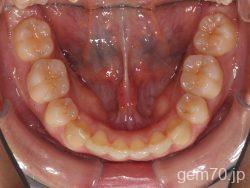

主訴)前歯のかみ合わせが深い

診断)過蓋咬合

使用装置)マルチブラケット装置(セラミックブラケット)

治療方法)4|4/4|4

治療期間) 2年8ヵ月 通院回数 32回